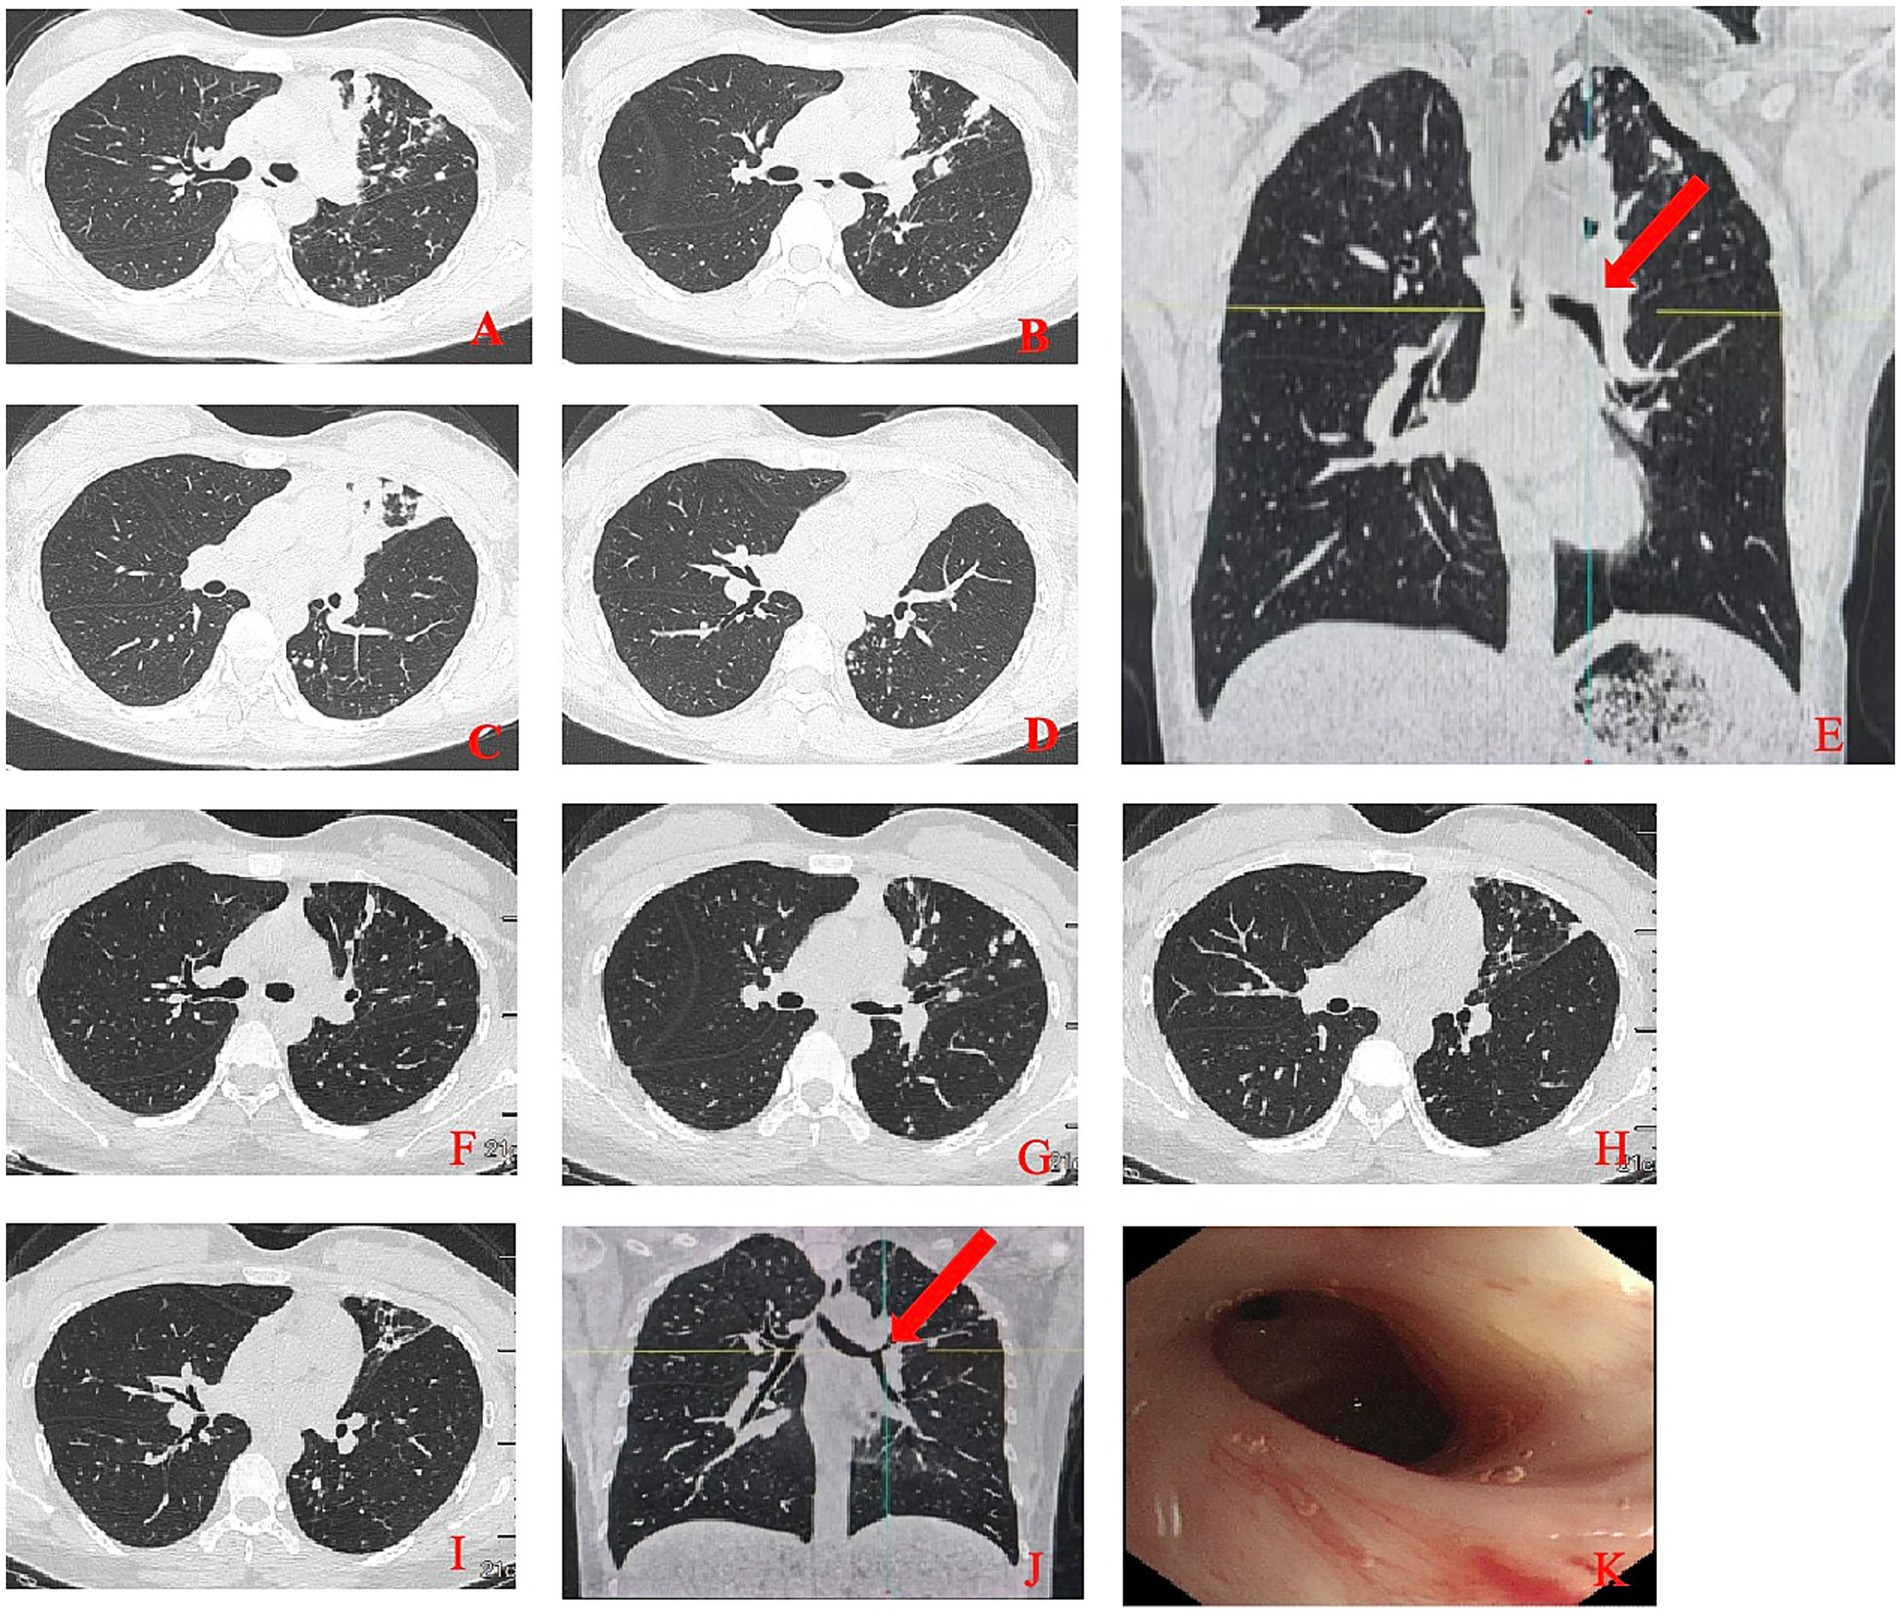

A 28-year-old female presented to our hospital on July 5, 2024, with a chief complaint of intermittent cough for 6 months, worsening over the past 20 days, and high fever for 1 day. She reported the onset of a dry, non-productive cough without any apparent trigger 6 months prior, with no associated symptoms such as fever, chest tightness, chest pain, or hemoptysis. She had sought medical attention at a local clinic 4 months earlier, where she received oral antibiotics and antitussive medications, resulting in slight symptom relief. Approximately 20 days before admission, her cough worsened, accompanied by low-grade afternoon fevers. A chest CT performed at a local hospital revealed multiple patchy opacities in the left lung. Bronchoscopic examination showed severe cicatricial stenosis at the orifice of the left upper lobe bronchus. Next-generation sequencing (NGS) of the bronchoalveolar lavage fluid was positive for Mycobacterium tuberculosis. Meanwhile, genetic mutation testing for first-line drug resistance revealed resistance to isoniazid. A diagnosis of pulmonary tuberculosis was made. One day before admission, the patient developed a sudden high fever, with a peak temperature of 40 °C, prompting her to seek emergency care at our facility, where she was admitted with a diagnosis of pulmonary tuberculosis. Physical examination revealed absent breath sounds in the left upper lung field, while breath sounds in the remaining lung fields were clear, with no audible dry or moist rales. The patient was alert and oriented, in good general condition, with normal appetite, sleep, bowel and bladder function, and no significant change in body weight. A chest CT scan performed after admission (Figures 1A–E) showed complete occlusion of the left upper lobe bronchus and multiple infectious lesions in the left lung. Bronchoscopic interventional therapy was planned as the proposed treatment approach.

Figure 1

Initial and follow-up chest CT Imaging with corresponding bronchoscopic findings. (A–E) Initial chest CT scan showed complete occlusion (arrow, E) of the left upper lobe bronchus and multiple infectious lesions in the left lung. (E–J) Follow-up chest CT showed significant resolution of the lesion (arrow, J) with a patent left upper lobe bronchus. (K) The left upper lobe bronchus with smooth mucosa and stable scar tissue.

After 8 months of treatment, chest CT reexamination (Figures 1F–J) showed significant resolution of the lesions and a patent left upper lobe bronchus. Bronchoscopic examination revealed a clear airway in the left upper lobe bronchus with smooth mucosa and stable scar tissue (Figure 1K). Although mild stenosis remained, it no longer impaired ventilation function, indicating a favorable long-term treatment outcome. During follow-up, the patient reported no significant cough or dyspnea, was able to carry out normal daily activities and work, and showed no signs of symptom recurrence, with a marked improvement in quality of life.